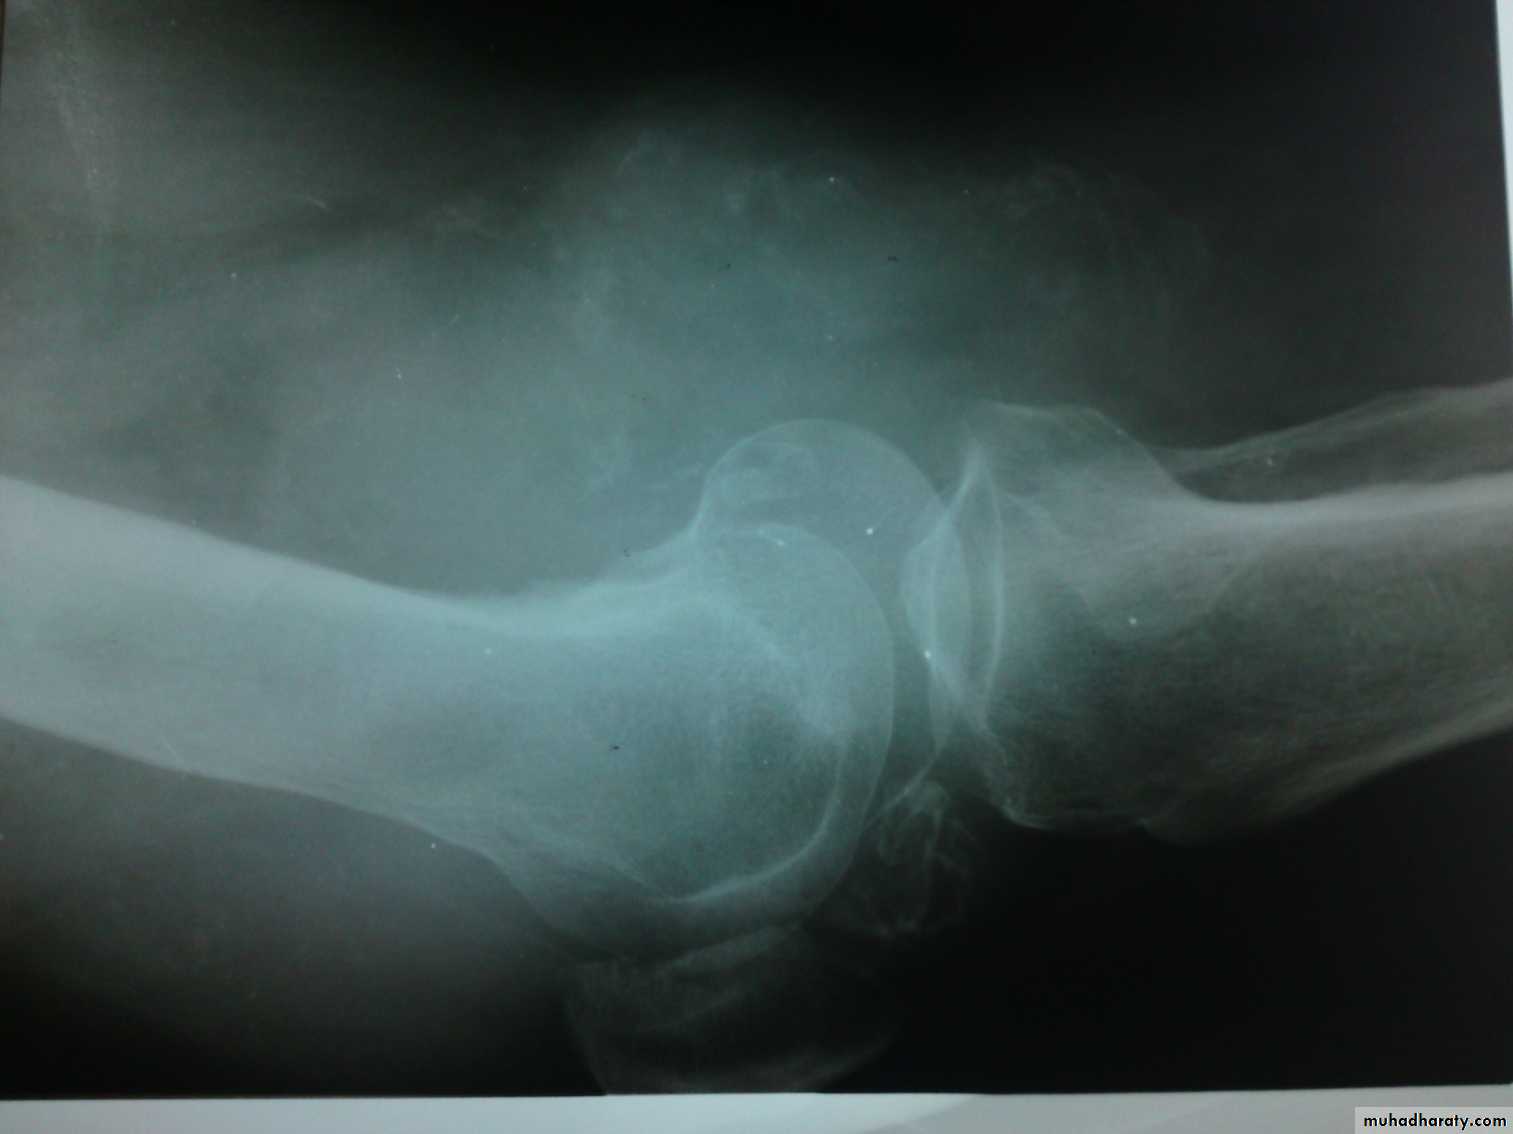

Shape:Decreased joint space and oseophytes in osteoarthritis.

Dislocation or subluxation.

Density: increased in chondrocalcinosis, loose bodies…